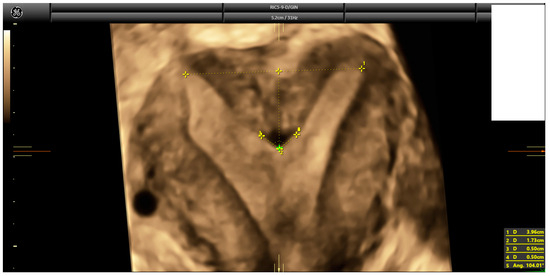

2.3. Ultrasound Evaluation

- Ludwin, A.; Martins, W.P. Correct measurements of uterine fundal internal indentation depth and angle: An important but overlooked issue for precise diagnosis of uterine anomalies. Ultrasound Obstet. Gynecol. 2021, 58, 497–499. [Google Scholar] [CrossRef] [PubMed]